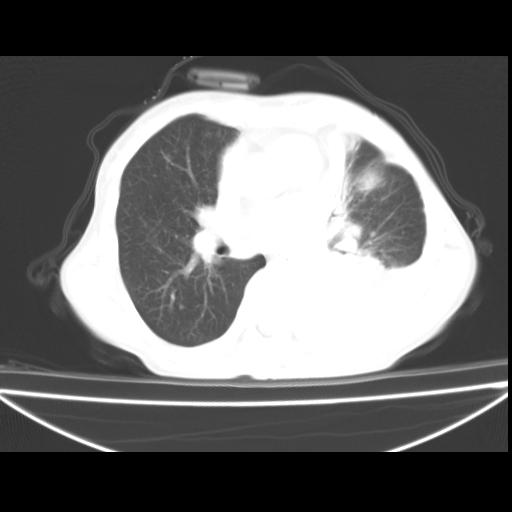

以下是引用zxl51642在2010-3-24 18:49:00的发言:[br]结合乳腺癌术后病史,考虑双肺及纵隔淋巴结多发转移、左侧胸膜转移并左侧大量胸水、左下肺膨胀不全。